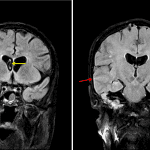

- FLAIR signal hyperintensity within multiple right temporal sulci with associated leptomeningeal enhancement in these areas

- Mild widespread cortical FLAIR signal hyperintensity and indistinctness

- Enhancing mass centered at the right jugular foramen measuring 2 x 2 cm

- Irregularity and hypoenhancement of the distal right transverse sinus and right sigmoid sinus

- T2/FLAIR signal hyperintensity in the right middle ear and right mastoidectomy bowl with associated enhancement

- Meningoencephalitis

Findings concerning for meningoencephalitis, particularly involving the right temporal lobe. Fluid signal in the right middle ear and mastoidectomy bowl could represent postoperative changes but could also be a source for intracranial infection. Recommend contrast-enhanced temporal bone CT to assess for bony dehiscence. No extraaxial collection or evidence of parenchymal abscess.

Patchy T2 hyperintense signal about the bilateral optic nerve sheaths with associated enhancement may represent subarachnoid spread of infection along the optic nerve sheaths.

Enhancing mass centered at the right jugular foramen measuring 2 x 2 cm suggestive of residual or recurrent tumor. Recommend correlation with prior imaging.

Irregularity and hypoenhancement of the distal right transverse sinus and right sigmoid sinus, which may represent postsurgical change or sequela of chronic thrombosis.